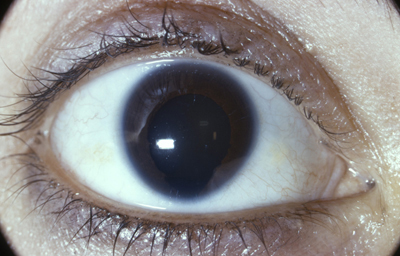

Es un término empleado al examen clínico, porque en todos los casos existen algunos rudimentos presentes al examen anatómico y microscópico; se asocia a mala visión, nistagmus y ausencia del reflejo foveal. (5,8)

Aniridia completa, catarata y distrofia corneal de la aniridia

Archivo Dr. Francisco Barraquer

Caso de paciente con Coloboma en un ojo y Aniridia en el contralateral

OD

Archivo Fotográfico Dr. Francisco Barraquer

OI

Archivo Dr. Francisco Barraquer